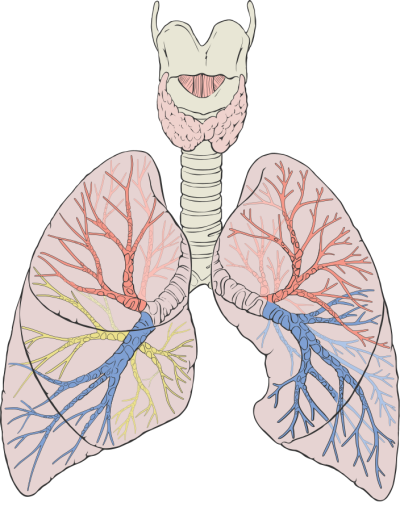

폐암은 폐에 비정상적인 암세포가 증식하여 덩어리를 형성하고 인체에 해를 미치는 것을 말합니다. 즉 폐에 생긴 악성종양을 말하며 폐 자체에 암이 발생하거나 다른 장기에서 생긴 암이 폐로 전이되어 발생합니다.